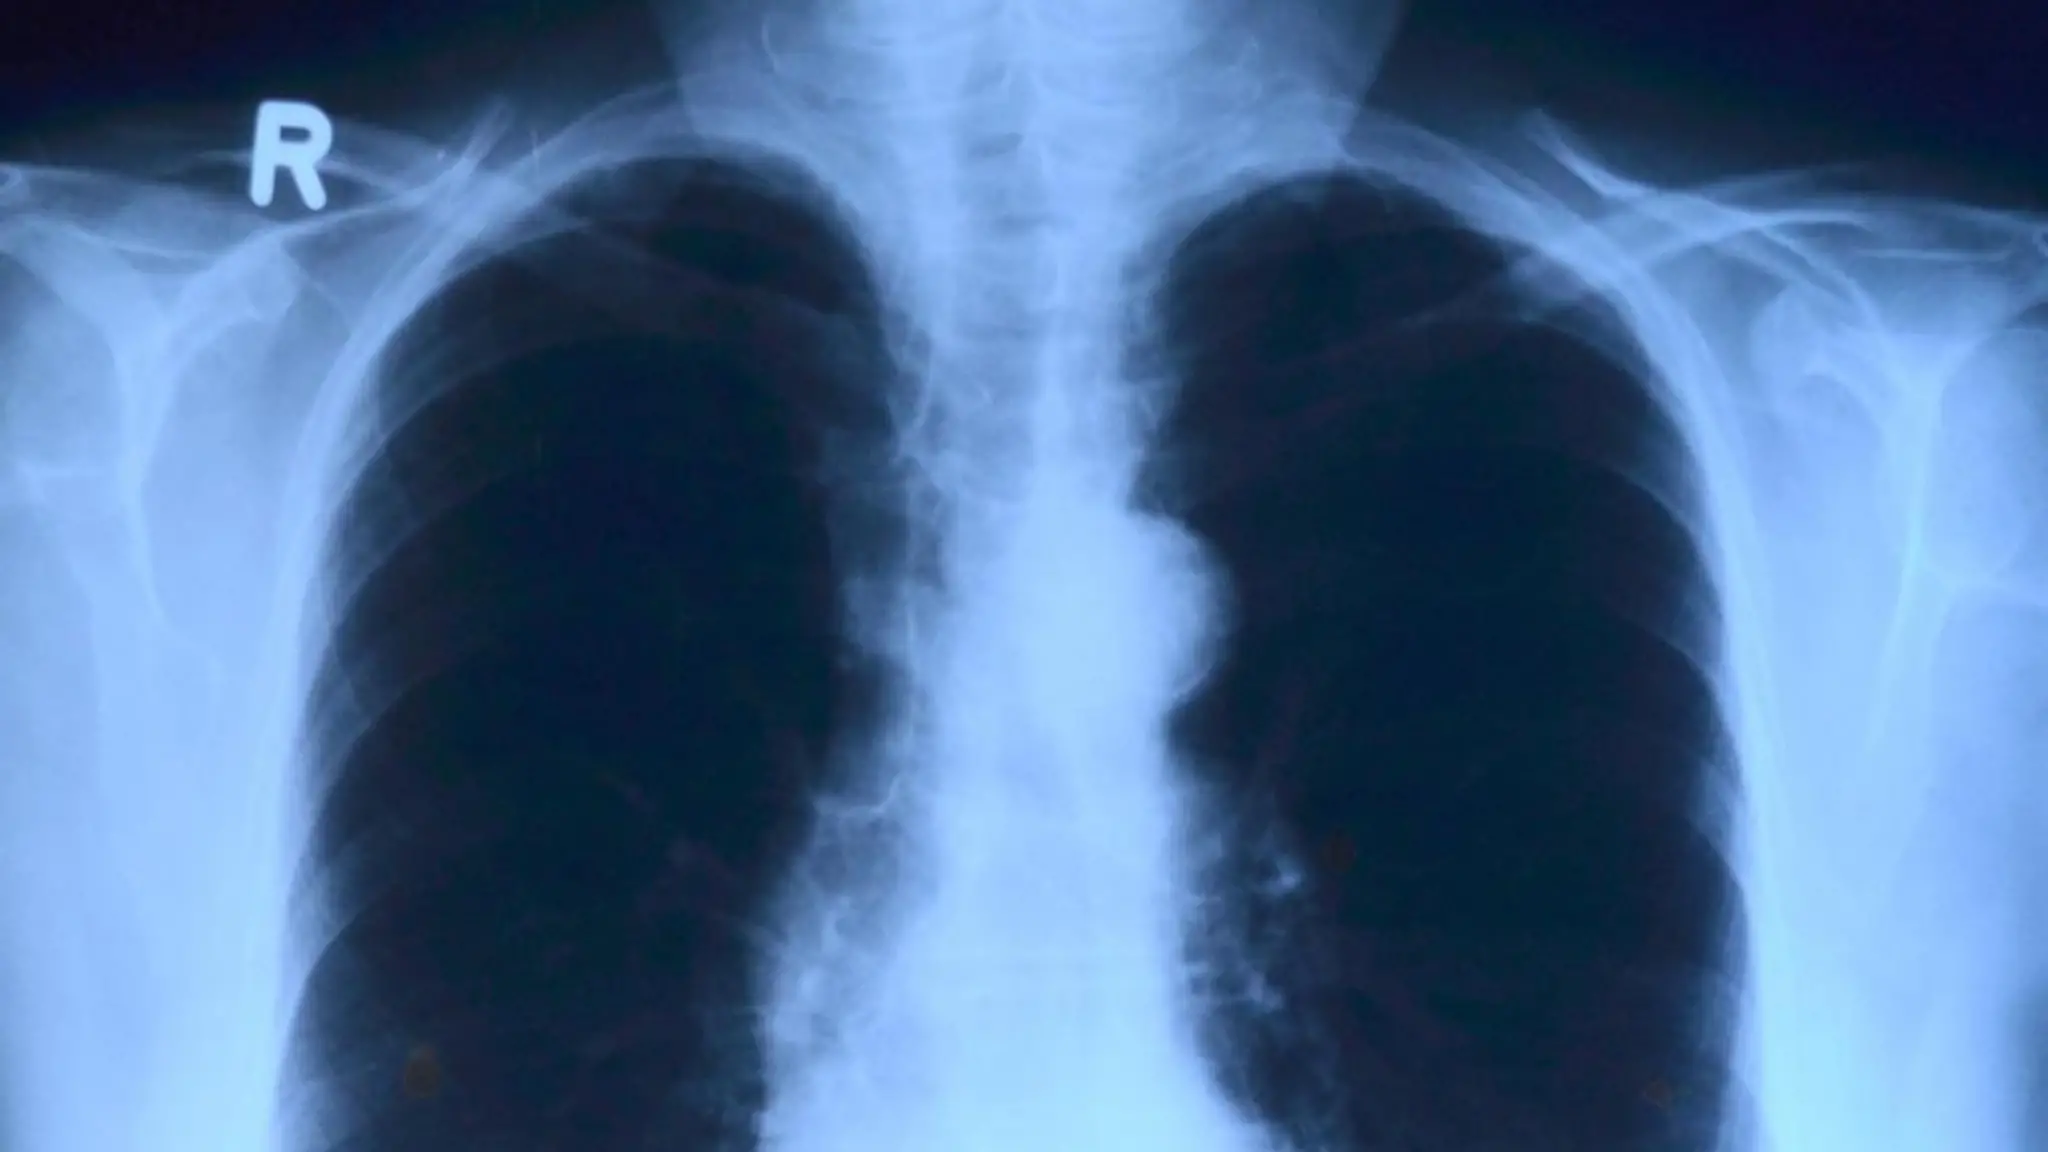

Tumori, aumentano nei giovani: in crescita neoplasie colon, pancreas e polmone

L'allarme del Policlinico Gemelli: "Per il colon +80% di casi under 50 entro il 2040"